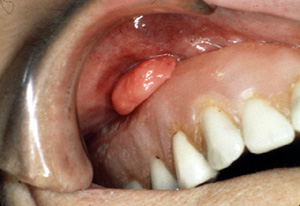

| Este épulis

fisurado se encuentra en una localización no habitual, en la

almohadilla retromolar.

Este

ejemplo extraño parece estar originando

porque la dentadura postiza irritaba la mucosa vestibular. |